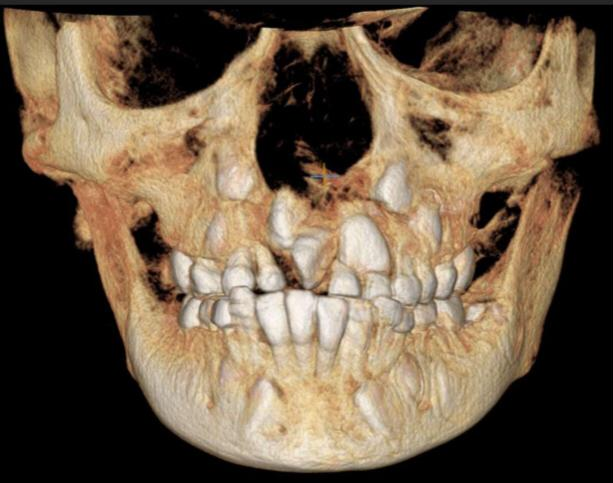

Tomografía Computarizada Cone Beam

Estudio tridimensional más preciso para evaluar condiciones específicas de la dentadura y huesos maxilares.